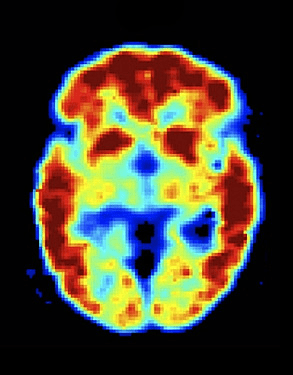

Foundational models for all modalities (MRI, PET, EEG, iEEG, MEG)

Foundational Models for (MRI, PET)